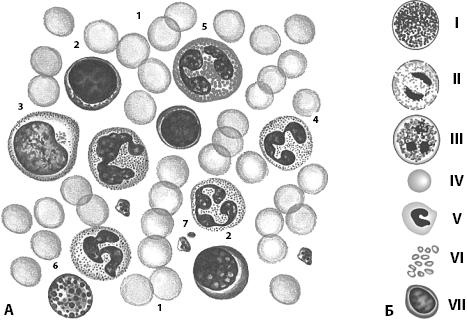

Белки плазмы крови (6,5–8,0 г/л, альбумины и глобулины) выполняют трофическую, транспортную, защитную, буферную функции; они также участвуют в свертывании крови и создании коллоидно-осмотического давления. На долю плазмы приходится около 54 % объема крови, на долю форменных элементов – около 44 %. В крови содержатся безъядерные клетки эритроциты (4,0–5,0) · 1012/л, лейкоциты (4,0–6,0) · 109/л, среди которых выделяют зернистые, или гранулоциты (нейтрофильные, ацидофильные и базофильные), а также незернистые, или агранулоциты (моноциты). В крови имеются также кровяные пластинки (тромбоциты), число которых составляет (180,0–320,0) · 109 в литре и лимфоциты, являющиеся структурными элементами лимфоидной системы (рис. 13).

Рис. 13. Кровь. А – мазок периферической крови взрослого человека (общий вид): 1 – эритроциты; 2 – лимфоциты; 3 – моноцит; 4 – нейтрофильные гранулоциты; 5 – эозинофильные гранулоциты; 6 – базофильные гранулоциты; 7 – тромбоциты; Б – клетки крови: I – базофильный гранулоцит; II – ацидофильный гранулоцит; III – сегментоядерный нейтрофильный гранулоцит; IV – эритроцит; V – моноцит; VI – тромбоциты; VII – лимфоцит